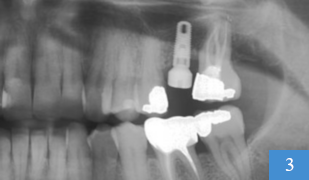

implant dentaire en place

3 : implant dentaire en place